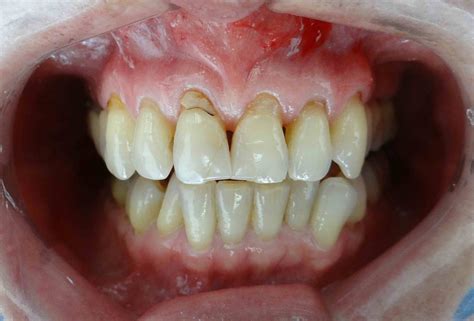

La retracción de las encías es una enfermedad periodontal en la que el tejido gingival que rodea al diente se desliza hacia arriba, dejando expuesta la raíz del diente. Las encías retraídas, también conocidas como recesión gingival, ocurren cuando el tejido que rodea los dientes se retira, revelando una mayor parte de la raíz del diente. Puede ocurrir en uno o en varios dientes a la vez.

Al retraerse el tejido, las encías lucen separadas de los dientes y se pueden formar bolsas en las que se acumula placa dental. Además, las piezas dentales lucen más alargadas, lo que afecta la sonrisa del paciente. Pero las consecuencias de las encías retraídas van más allá de la estética, ya que también pone en riesgo la salud dental en general.

- Dientes alargados: Uno de los signos visuales más evidentes de las encías retraídas es la apariencia de dientes alargados. La retracción del tejido gingival revela más parte de la superficie dental, afectando la estética de la sonrisa.